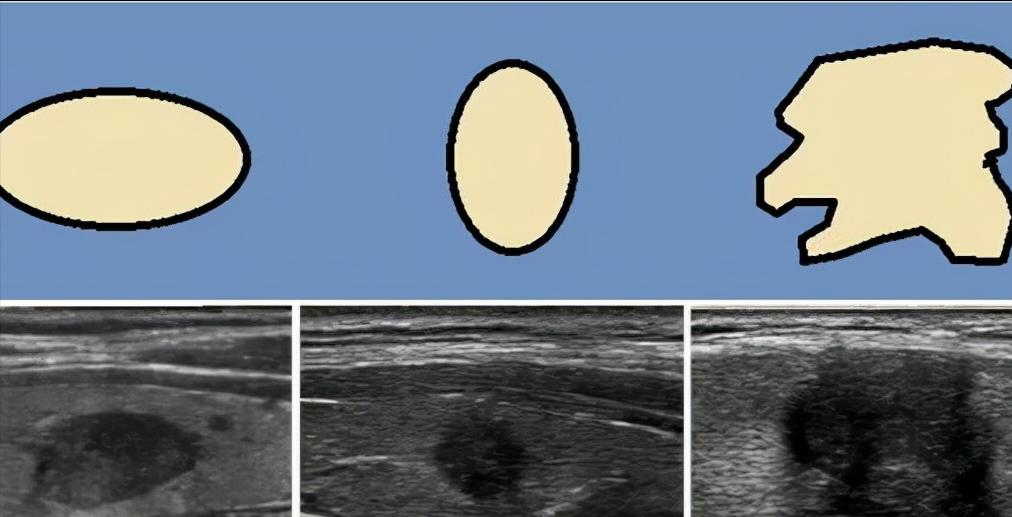

一般在临床上我们看到的囊性的结节,

囊性的其内是液体,一般反应是无回声,

如果是一个实性结节那反应的就是低回声,

临床上不能仅依靠回声这一个指标来判断结节的良恶性,

要结合边界、形态、血流、纵横比、有无毛刺等等多方面综合评定。